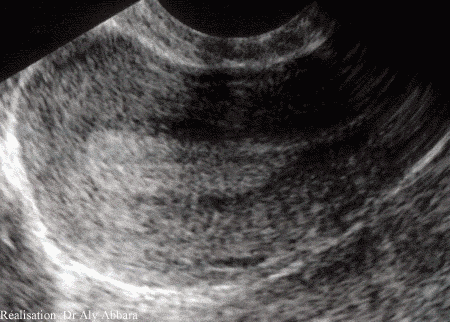

Utérus chez une femme adulte

Coupe sagittale montrant ses différents

éléments anatomiques